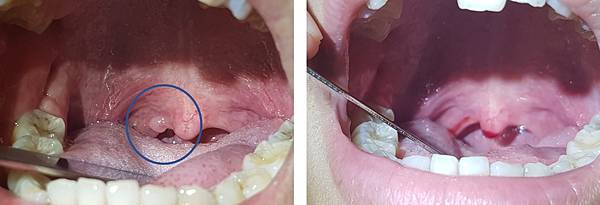

她很擔心,怎麼這麼年輕就得到腫瘤。經過詳細檢查,發現在她的懸壅垂(俗稱小舌或喉嚨滴ㄚ),有一個小小的腫塊,於是直接在門診幫她切除,並送化驗。

報告結果如同我想的一樣,乳突瘤!!